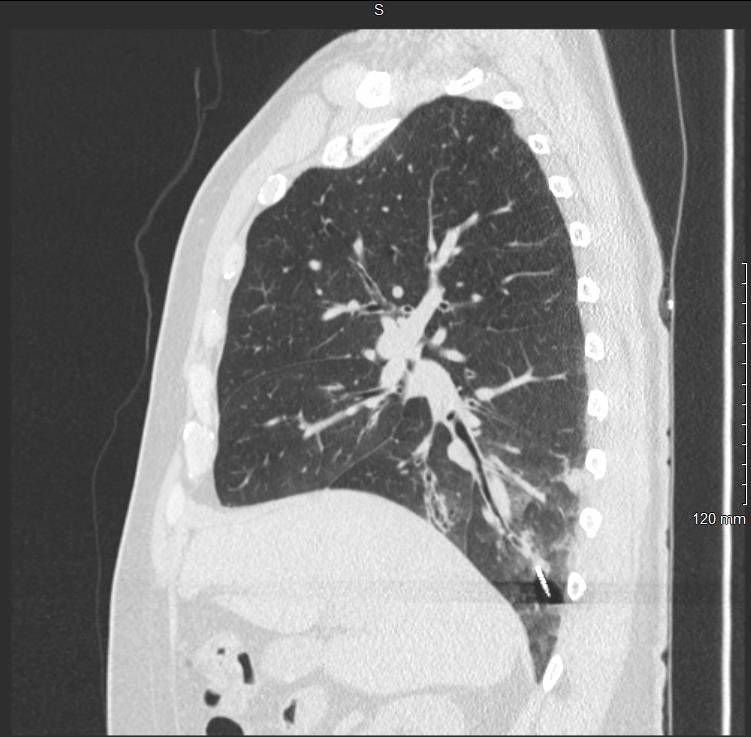

Ramsy Abdelghani, MD@Rabdelgh·

Cool case: 4.5mm partially solid PET-Avid LLL nodule. Used High PEEP/Tidal volume and wedged left side up to decrease dependent atelectasis. Navigated with Ion and adjusted with Philips CBCT. ROSE positive for Adenocarcinoma. Exciting times in lung cancer care! #ION #cbct